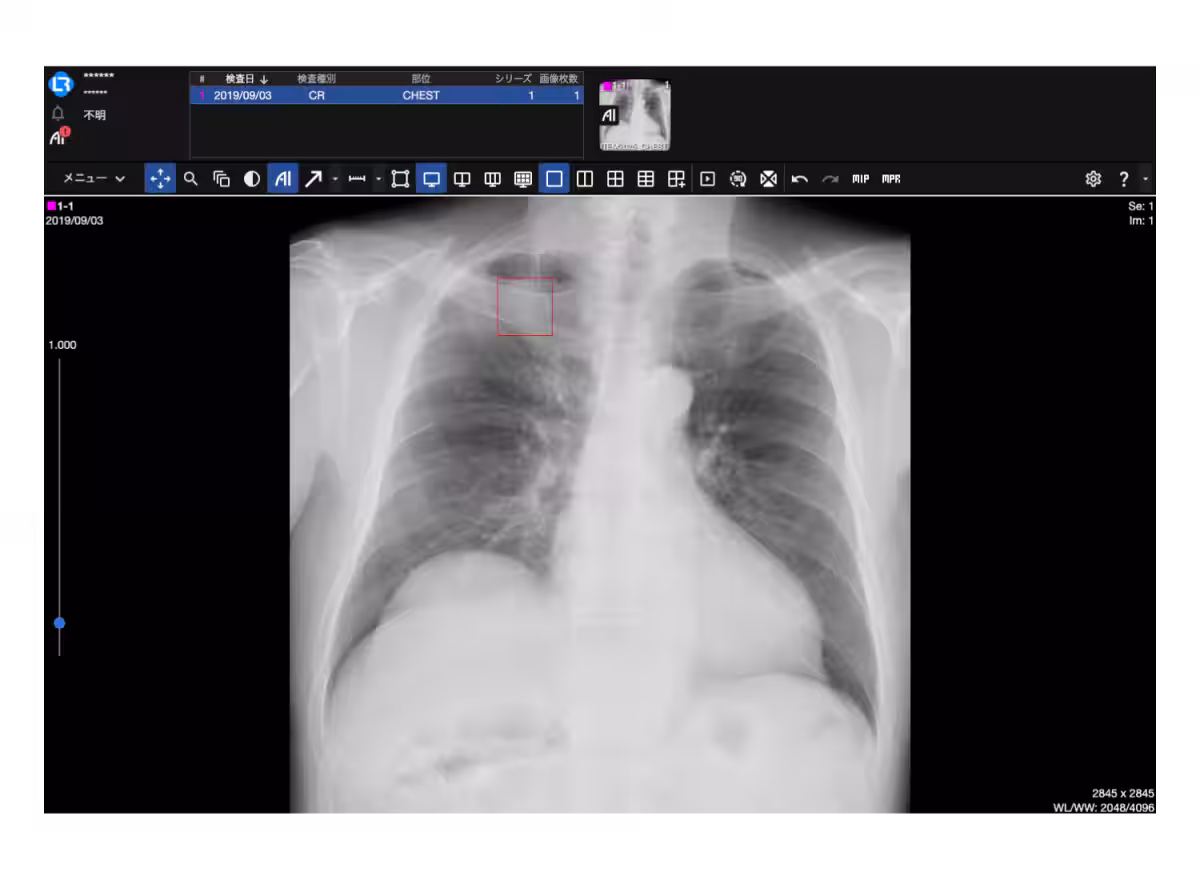

LOOKRECは、CTやMRIなどの医療機器から得られた画像をクラウドにアップロードし、リアルタイムで閲覧や共有ができるDICOMデータプラットフォームです。これをエルピクセルの画像診断支援AI「EIRL」とAPIで連携させることで、医療現場における診断の迅速化を実現します。

エルピクセルが提供するEIRLは、画像診断を支援するAIです。「医療AIですべての人に健康な未来を」という理念の下、1,200万件以上の解析実績があります。特に、クリニック向けに導入コストが更に低減されたクラウド型「EIRL Cloud」も発表され、利便性が向上しましたが、手動でのデータ作業が必要でした。

今回のAPI連携により、LOOKRECを使用している医療機関では、データの送受信を自動で行うことができ、ユーザビリティが格段に向上します。これにより、医師がより多くの時間を患者ケアに注ぐことができるようになるでしょう。

新しいプランでは、胸部X線に関連するEIRL Chest XRや、肺の結節を評価するEIRL X-Ray Lung nodule、さらには頭部MRAに対応しているEIRL Brain Aneurysmが利用可能になりました。これにより、医療現場での診断支援AIの活用範囲が広がり、医師たちが日常の診断業務をより効率的に行えるようになります。